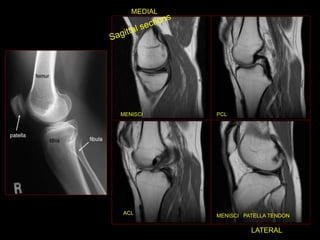

RM JOELHO

 Entorse

 Rompimento dos

ligamentos cruzados

anteriores e posteriores.

 Exame ouro pra estudo

do joelho.

LCA E LCP

LIGAMENTO CRUZADO

-

MENISCI PCL

ACL

MENISCI PATELLA TENDON

MEDIAL

LATERAL